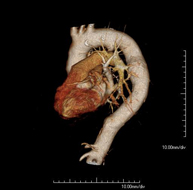

- Thoracic aorta CT angiography

Diagnostic test to examine the thoracic aorta (main artery of the thorax) using CT (Computed Tomography) equipment. This technique requires the use of an iodinated contrast agent, and provides high definition anatomical images. The use of MDCT (Multidetector Computed Tomography) shortens scanning time, reduces radiation dose and improves image quality. The multiple detectors used in certain studies enable imaging to be synchronised with the heartbeat, a technique used to study the aortic valve and aortic root (the first few centimetres), where the heartbeat often distorts images due to movement.